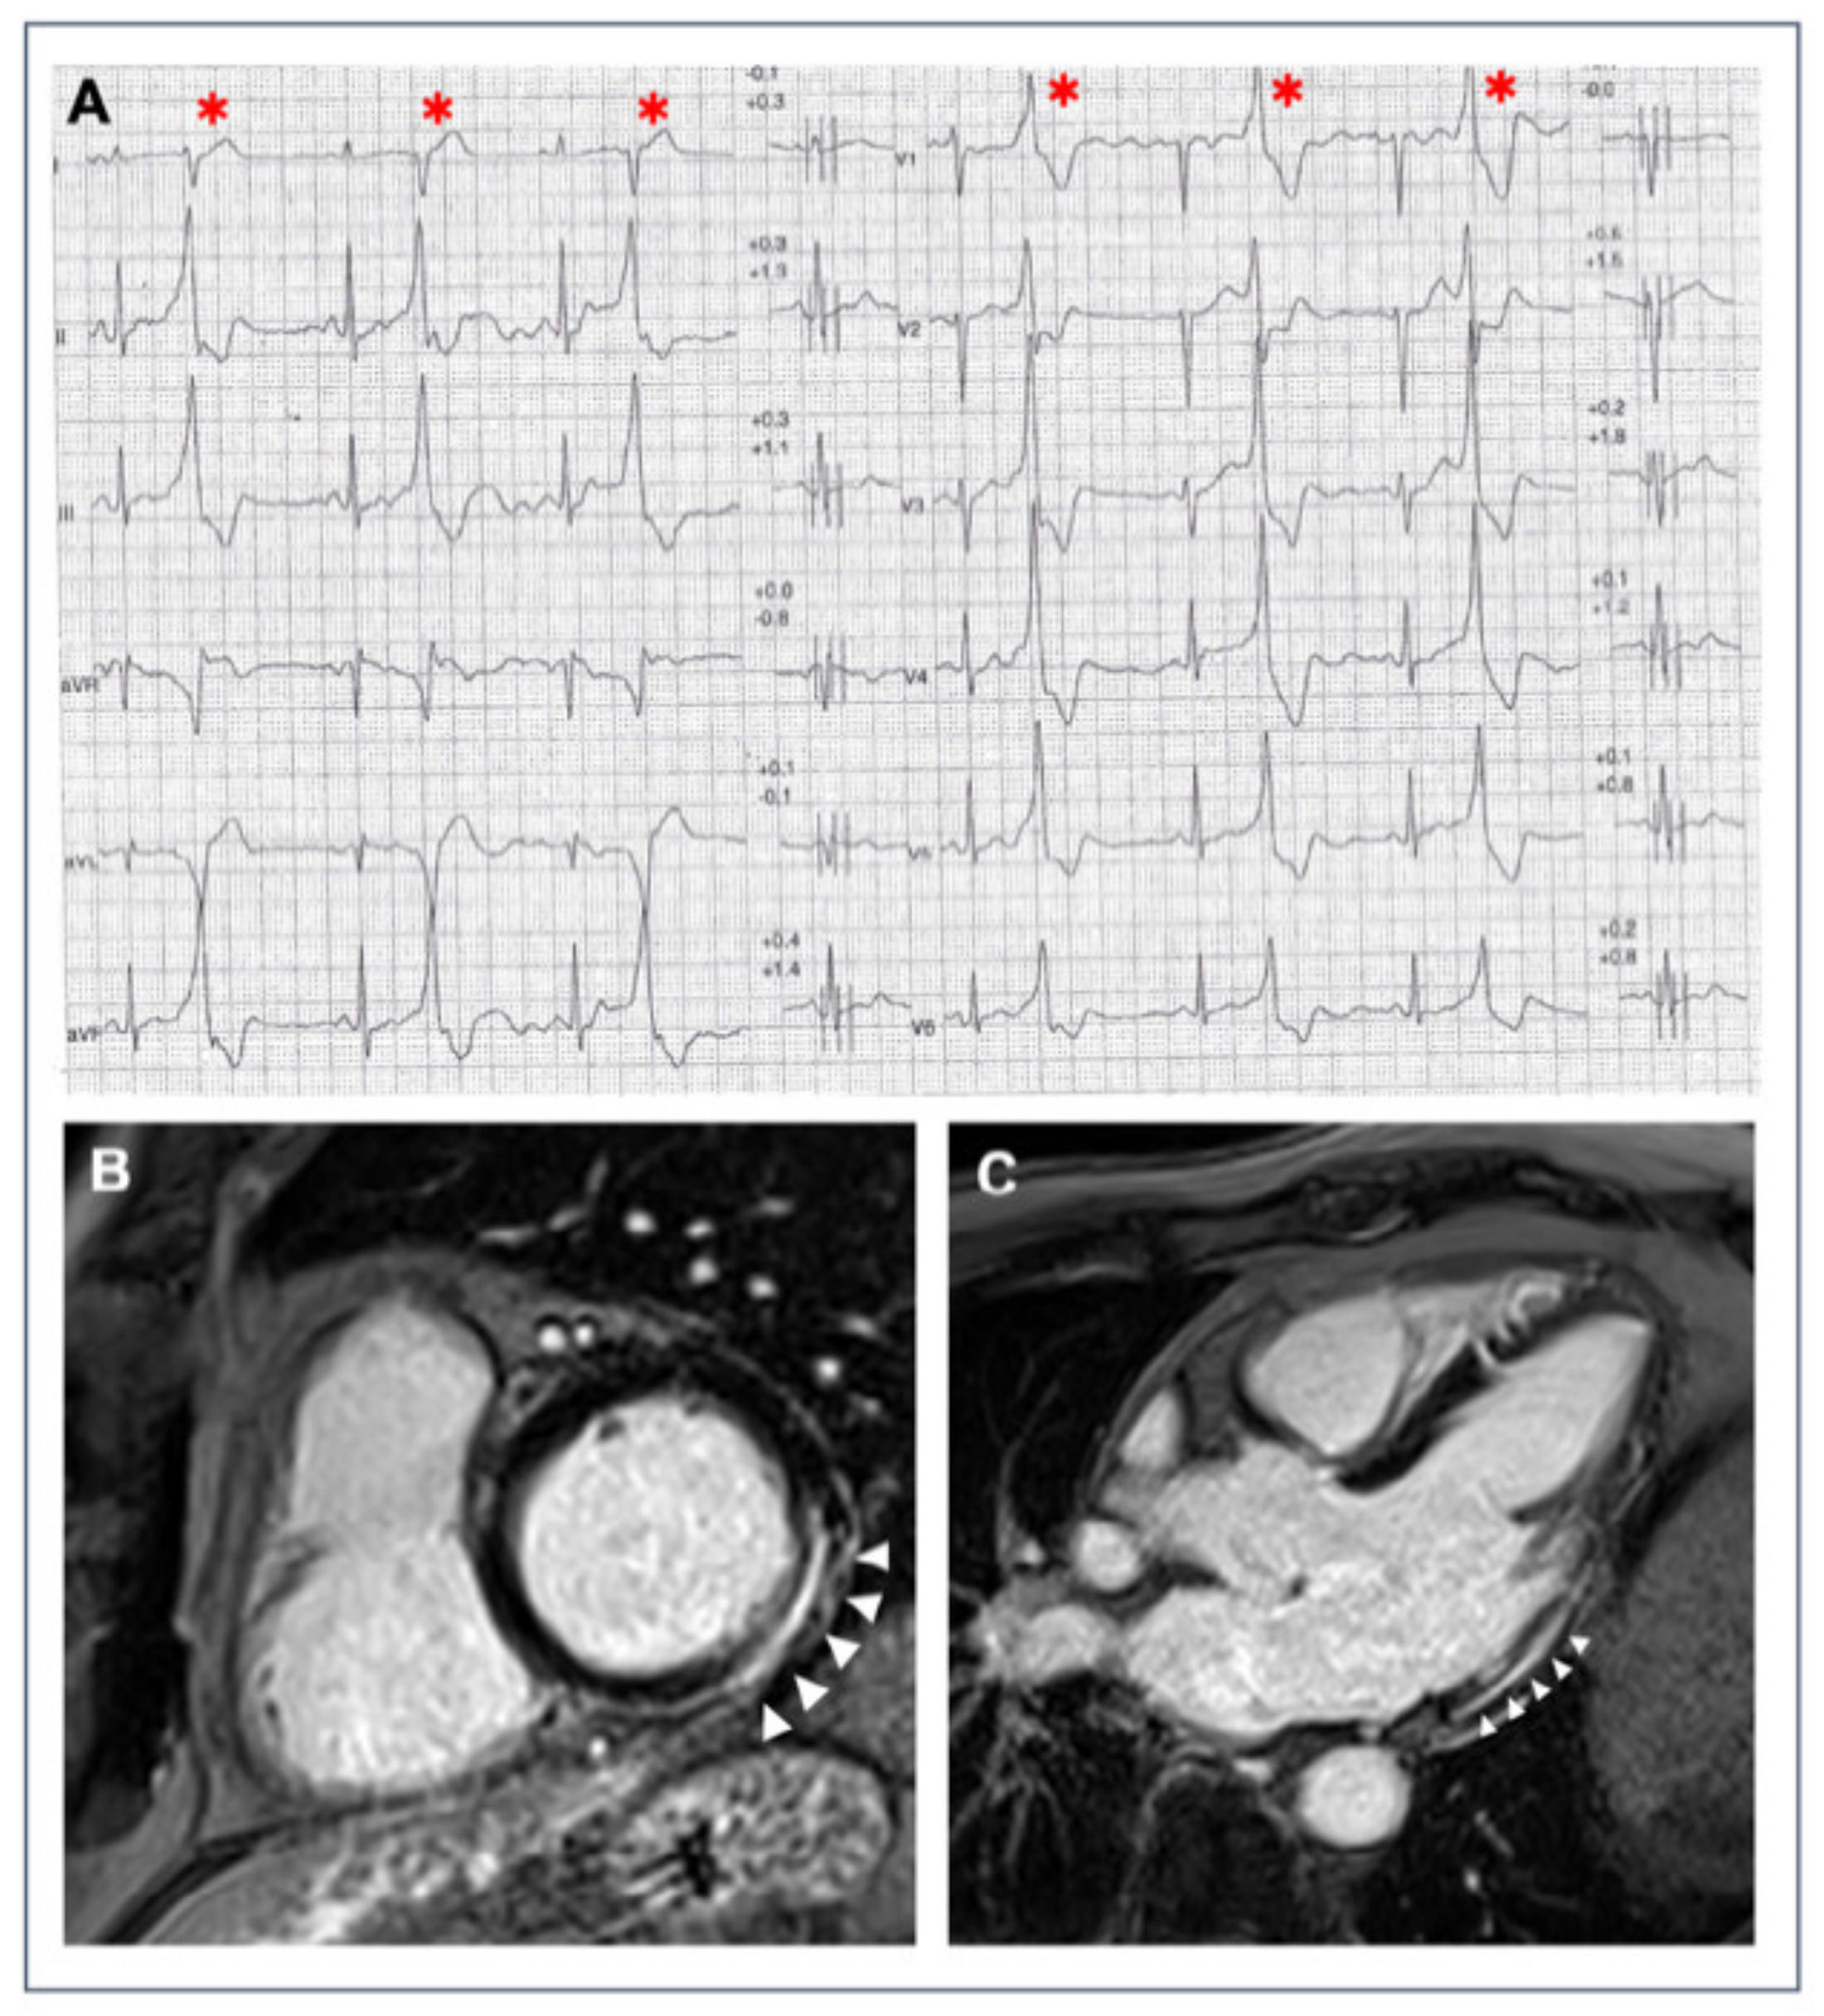

- Zorzi, A.; Marra, M.P.; Rigato, I.; De Lazzari, M.; Susana, A.; Niero, A.; Pilichou, K.; Migliore, F.; Rizzo, S.; Giorgi, B.; et al. Nonischemic left ventricular scar as a substrate of life-threatening ventricular arrhythmias and sudden cardiac death in competitive athletes. Circ. Arrhythmia Electrophysiol. 2016, 9, e004229. [Google Scholar] [CrossRef]

- De Lazzari, M.; Zorzi, A.; Cipriani, A.; Susana, A.; Mastella, G.; Rizzo, A.; Rigato, I.; Bauce, B.; Giorgi, B.; Lacognata, C.; et al. Relationship between electrocardiographic findings and cardiac magnetic resonance phenotypes in arrhythmogenic cardiomyopathy. J. Am. Heart Assoc. 2018, 7, e009855. [Google Scholar] [CrossRef]